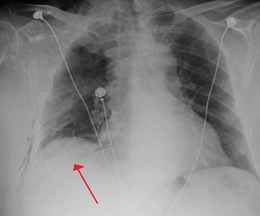

A large right-sided spontaneous pneumothorax (left in the image). An arrow indicates the edge of the collapsed lung

Chest X-ray showing the features of pneumothorax on the left side of the person (right in image)

A plain chest radiograph, ideally with the X-ray beams being projected from the back (posteroanterior, or "PA"), and during maximal inspiration (holding one's breath), is the most appropriate first investigation.[25] It is not believed that routinely taking images during expiration would confer any benefit.[26] Still, they may be useful in the detection of a pneumothorax when clinical suspicion is high but yet an inspiratory radiograph appears normal.[27] Also, if the PA X-ray does not show a pneumothorax but there is a strong suspicion of one, lateral X-rays (with beams projecting from the side) may be performed, but this is not routine practice.[14][18]

The size of the pneumothorax (i.e. the volume of air in the pleural space) can be determined with a reasonable degree of accuracy by measuring the distance between the chest wall and the lung. This is relevant to treatment, as smaller pneumothoraces may be managed differently. An air rim of 2 cm means that the pneumothorax occupies about 50% of the hemithorax.[14] British professional guidelines have traditionally stated that the measurement should be performed at the level of the hilum (where blood vessels and airways enter the lung) with 2 cm as the cutoff,[14] while American guidelines state that the measurement should be done at the apex (top) of the lung with 3 cm differentiating between a "small" and a "large" pneumothorax.[28] The latter method may overestimate the size of a pneumothorax if it is located mainly at the apex, which is a common occurrence.[14] The various methods correlate poorly but are the best easily available ways of estimating pneumothorax size.[14][18] CT scanning (see below) can provide a more accurate determination of the size of the pneumothorax, but its routine use in this setting is not recommended.[28]

Not all pneumothoraces are uniform; some only form a pocket of air in a particular place in the chest.[14] Small amounts of fluid may be noted on the chest X-ray (hydropneumothorax); this may be blood (hemopneumothorax).[13] In some cases, the only significant abnormality may be the "deep sulcus sign", in which the normally small space between the chest wall and the diaphragm appears enlarged due to the abnormal presence of fluid.[15]